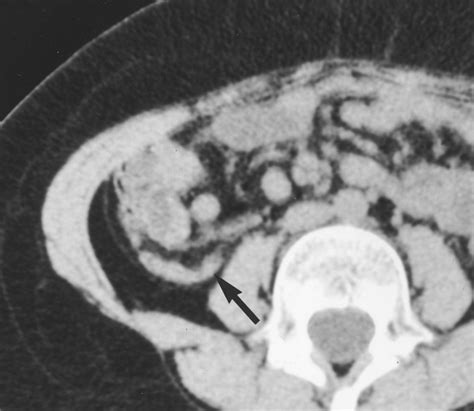

Radiologists look for specific markers when evaluating a CT scan for appendicitis. These indicators are crucial for confirming an acute inflammatory process within the appendix. The following findings are commonly associated with the diagnosis:

• Appendix Diameter: A normal appendix is typically 6 millimeters or less in diameter. If the diameter exceeds this threshold, it is a primary indicator of distention and inflammation.

• Wall Thickening: Inflammation causes the muscular wall of the appendix to thicken. This is often highlighted when intravenous contrast dye is used.

• Periappendiceal Fat Stranding: This appears as hazy, gray density surrounding the appendix, indicating that the inflammation has begun to spread into the surrounding fatty tissue.

• Appendicoliths: These are calcified deposits (fecal stones) within the appendix that can obstruct the lumen, leading to infection.

• Extraluminal Fluid: The presence of free fluid around the appendix or in the pelvic cavity suggests that the appendix may be perforated or severely inflamed.

Ultimately, the accuracy of the diagnosis relies on the synergy between the clinical presentation and the imaging report. A skilled radiologist will examine the entire image set, checking for "the target sign"—a specific appearance where the appendix looks like a circular target due to the layers of the inflamed wall—as well as the previously mentioned fat stranding and wall thickening.